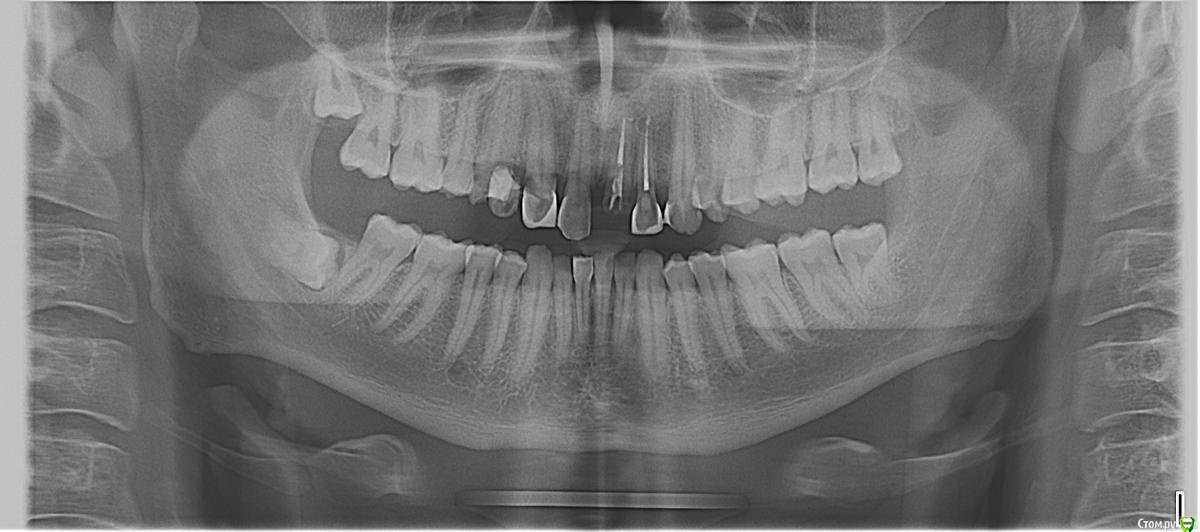

Алексей_1989 Опубликовано 5 августа, 2019 Поделиться Опубликовано 5 августа, 2019 Здравствуйте, будьте добры, подскажите пожалуйста: Мне 30 лет, 10 лет назад у меня была киста на месте выбитого зуба. Мне ее вырезали поставили коронку. Недавно коронка выпала. Я решил поставить. Мне сказали, что с таким прикусом ставить нельзя. Нижние зубы бьют по коронке. Я и сам это чувствую, нижние зубы уже и бьют по нормальным передним зубам. Ортодонт в клинике сказал, что надо иправлять прикус, но что он у меня очень глубокий и брейкеты мне не помогут. Нужно наплавлять на боковые зубы коронки, чтоб поднять прикус и все. Я решил сходить к еще одному ортодонту к другой клинике....все наоборот.. только брейкеты, они одни помогут, наплавлять ничего не надо, еще и потому, что последний ортодонт мне сказал, что от поднятия так зубов, передние зубы никак друг с другом не будут соприкасаться и от этого могут быть ПРОБЛЕМЫ С ПОЗВОНОЧНИКОМ! ГРЫЖИ, ПРОТРУЗИИ! Так что если нет желание еще больших проблем - нужны брейкеты....вот это да....Я не понимаю кому верить тут.Вы не могли бы посмотреть на мой панорамный снимок (если он поможет, если надо какой-то еще снимок или что-то еще - я сделаю) брейкеты или увеличивать боковые зубы? Ссылка на комментарий

Алексей_1989 Опубликовано 14 августа, 2019 Автор Поделиться Опубликовано 14 августа, 2019 Был у еще однного ортодонта. Тот сказал, что брейкеты ставить обязательно. А вот нужно ли еще и наплавлять - отправил на исследование под названием "Рентгеновская томография височно-нижнечелюстных суставов (с октрыи ртом и привычной окклюзии)Вот такие снимки я получил. Вы не могли бы сказать, по ним видно, можно ли обойтись только брейкетами? Ссылка на комментарий